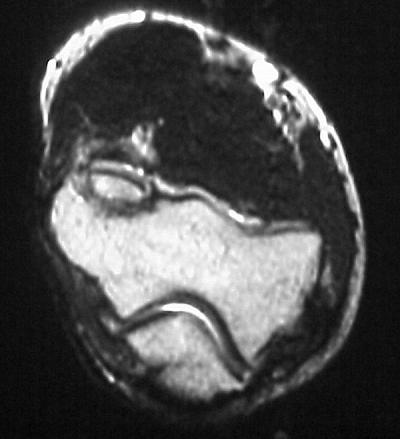

MRI shows an osteochondral sequestrum of the anterior capitellum:

Click for larger image